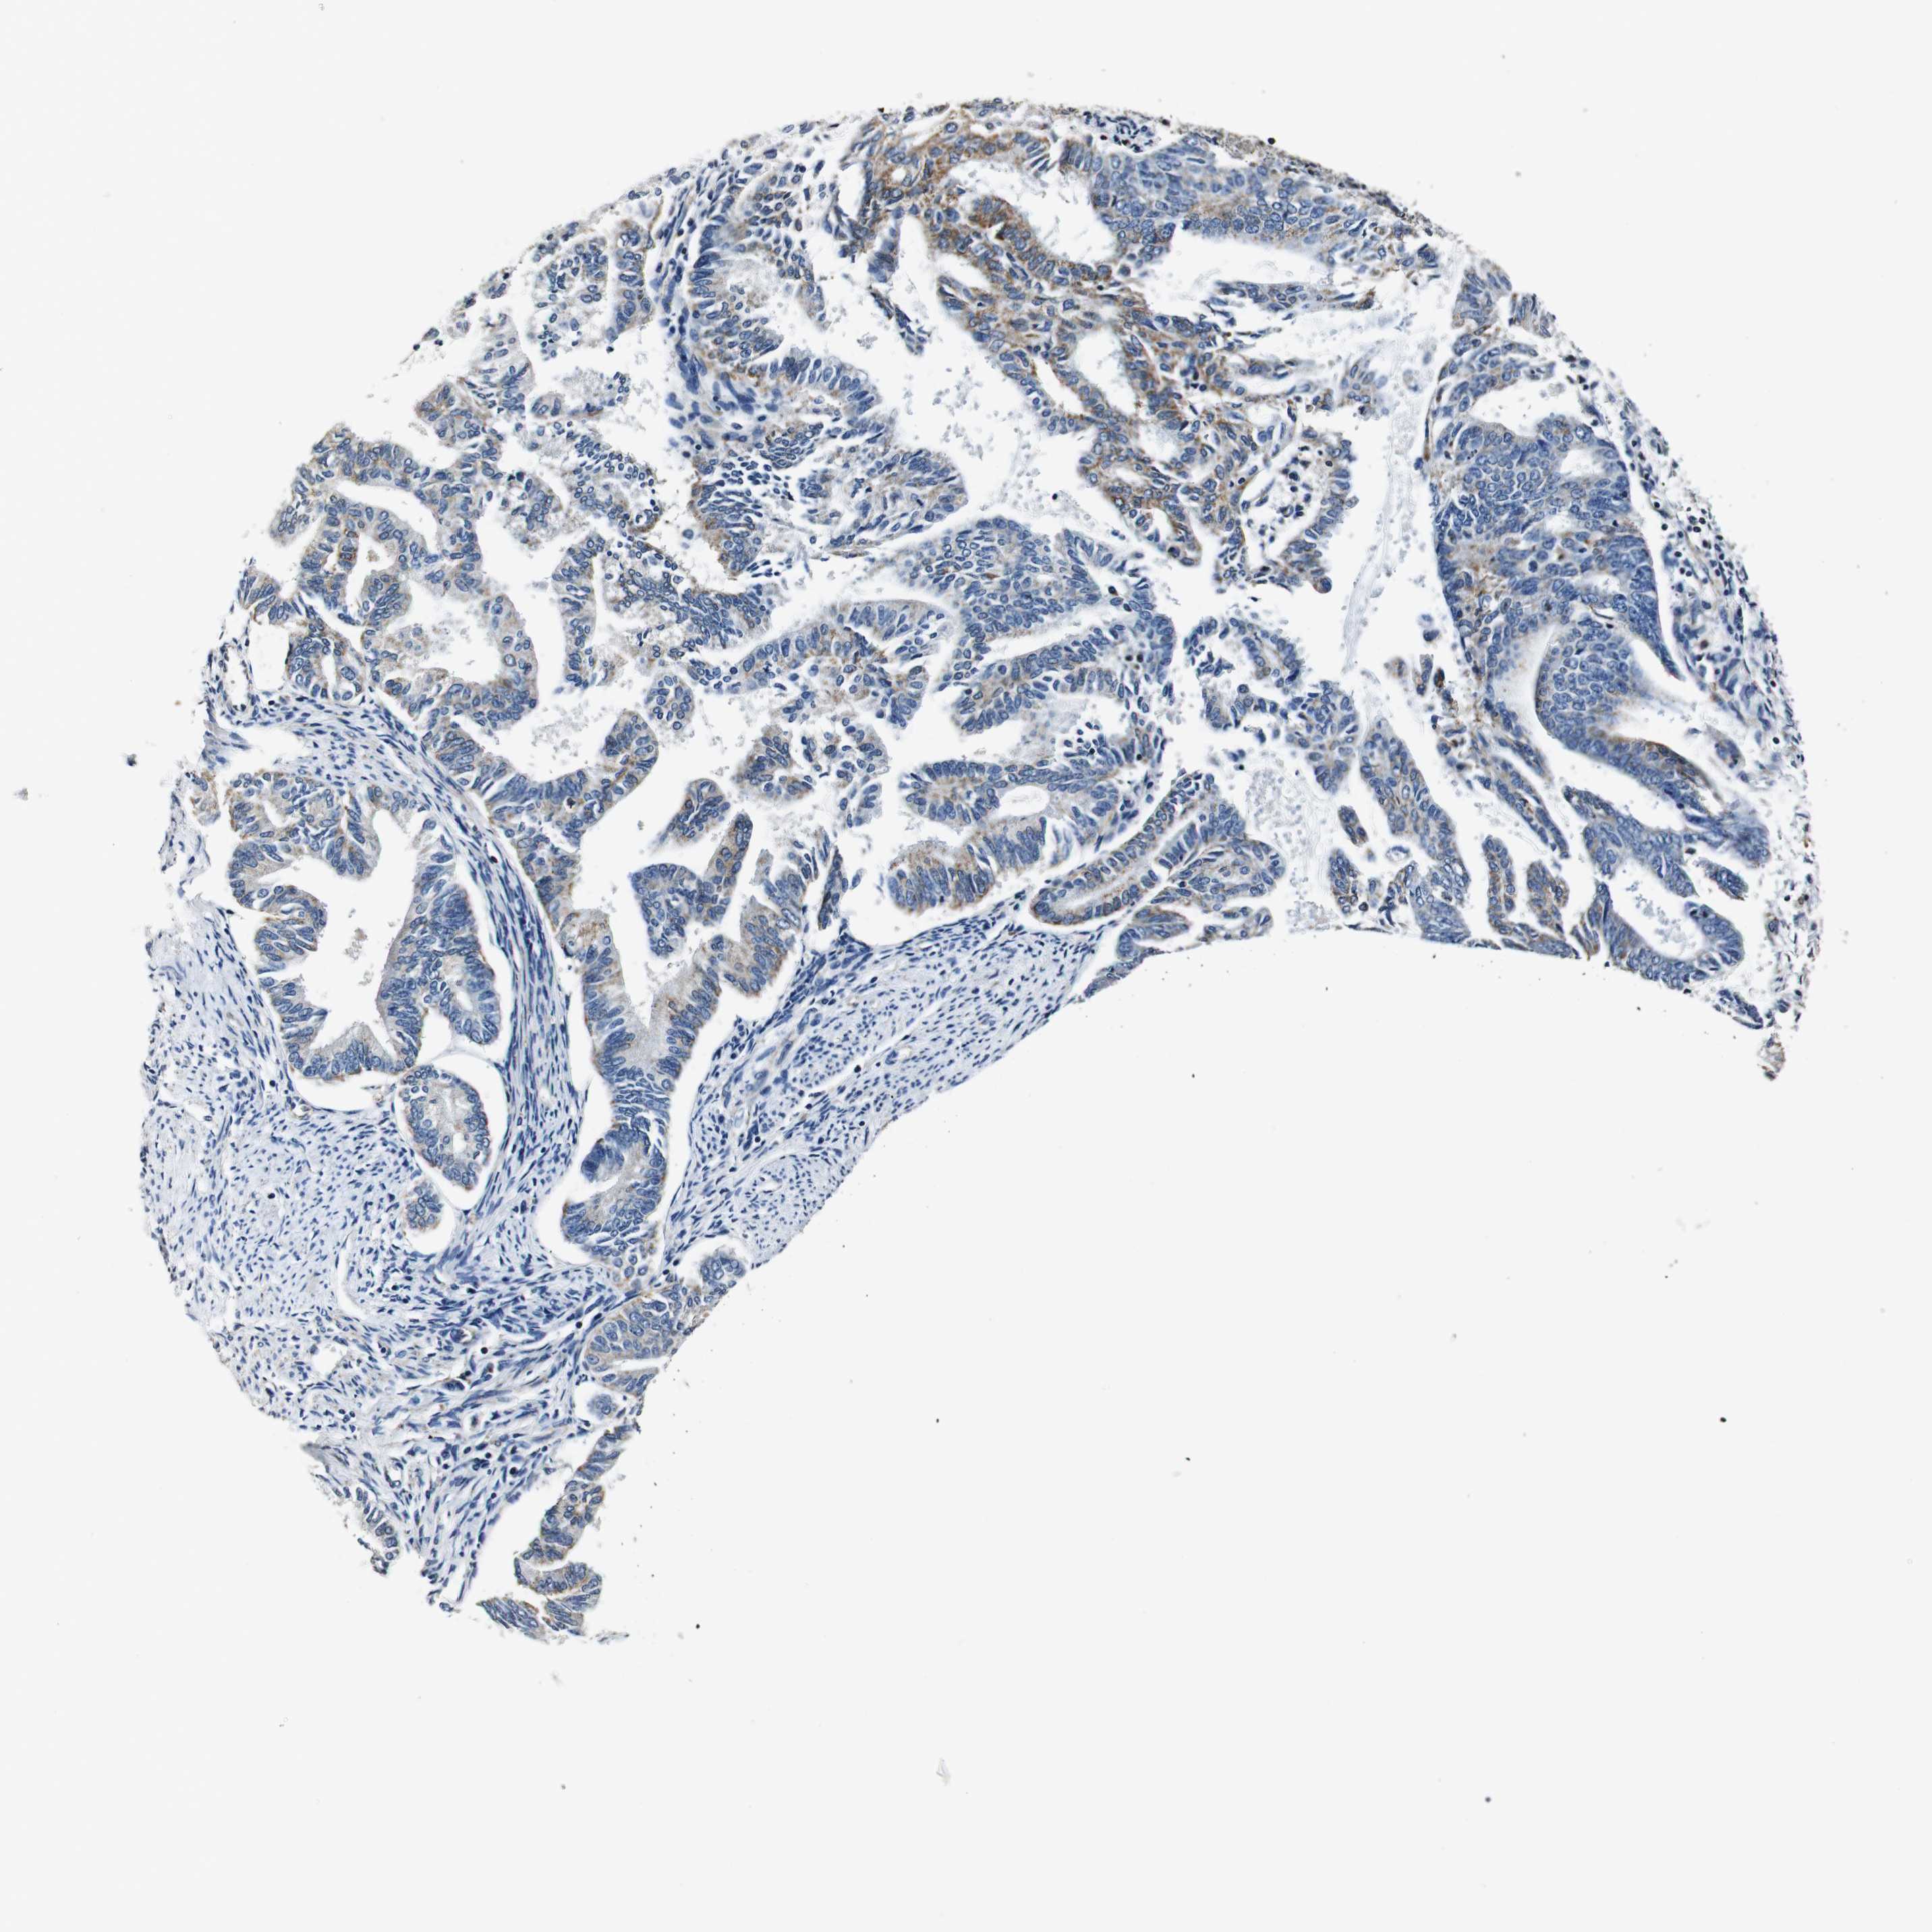

ENDOMETRIAL CANCER - Protein expressioni

A mouse-over function shows sample information and annotation data. Click on an image to view it in a full screen mode. Samples can be filtered based on level of antibody staining by selecting one or several of the following categories: high, medium, low and not detected. The assay and annotation is described here.

Note that samples used for immunohistochemistry by the Human Protein Atlas do not correspond to samples in the TCGA dataset.

Antibody stainingi

Antibody staining in the annotated cell types in the current human tissue is reported as not detected, low, medium, or high, based on conventional immunohistochemistry profiling in selected tissues. This score is based on the combination of the staining intensity and fraction of stained cells.

Each image is clickable and will lead to virtual microscopy that enables deeper exploration of all samples and also displays staining intensity scores, fraction scores and subcellular localization as well as patient and tissue information for each sample.

Antibody HPA007043

Antibody HPA007044

Antibody CAB010052

Staining

High

Medium

Low

Not detected

Intensity

Strong

Moderate

Weak

Negative

Quantity

>75%

75%-25%

<25%

None

Location

Nuclear

Cytoplasmic/membranous

Cytoplasmic/membranous,nuclear

Adenocarcinoma, NOS